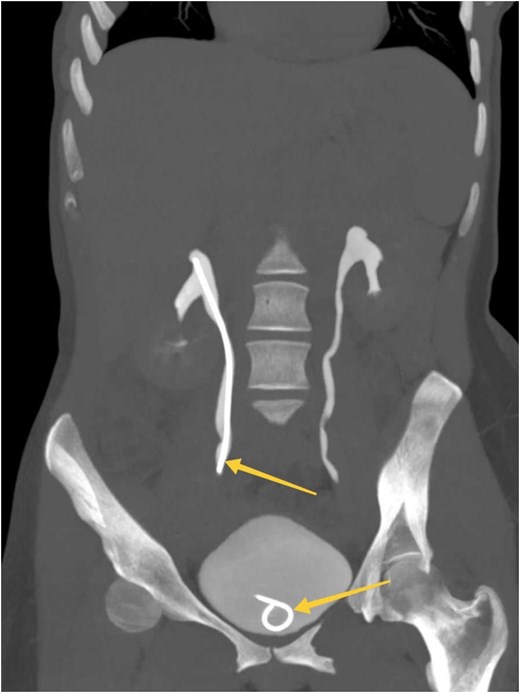

Postoperatively, the patient was admitted for monitoring and received intravenous fluids, analgesics, and antibiotics. Her clinical condition improved significantly, and follow-up imaging showed resolution of the obstruction and extravasation (Fig. 2). She was discharged in good clinical condition, with no pain or urinary symptoms. At the one-month follow-up, the D-J stent was removed without complications. The patient reported no recurrence of symptoms, and her clinical outcomes remained good.

MIP reconstructed coronal images of contrasted CT scan obtained at delayed phases (bone window) showing symmetrical bilateral renal excretion with D-J stent in the right ureter and bladder (arrows).